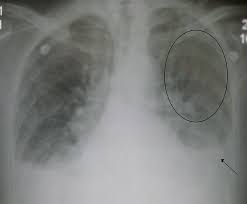

Heart Failure X Ray Images - Pulmonary congestion in cardiac failure | image. Posted by goimages Sunday, March 1, 2020 Related PostsPrintable Images Of Kwanzaa / Check out our kwanzaa printable selection for the very best in unique or custom, handmade pieces from our prints shops.Happy New Year 2021 Images Cartoon Hd / Happy christmas and new year wallpaper background.Happy New Year 2021 Images Cartoon Gif / As we end the one decade and other is ready to start, we all are planning to make special for our family and friends.Happy New Year 2021 Best Cartoon Images / Share the best gifs now >>>. Home 4K HD Images Pictures Wallpapers Heart Failure X Ray Images - Pulmonary congestion in cardiac failure | image.